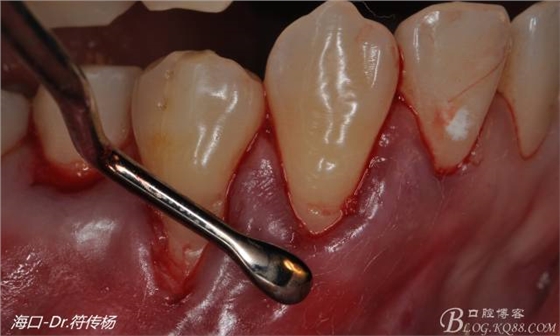

然后使用下頜開隧刀剝離牙齦